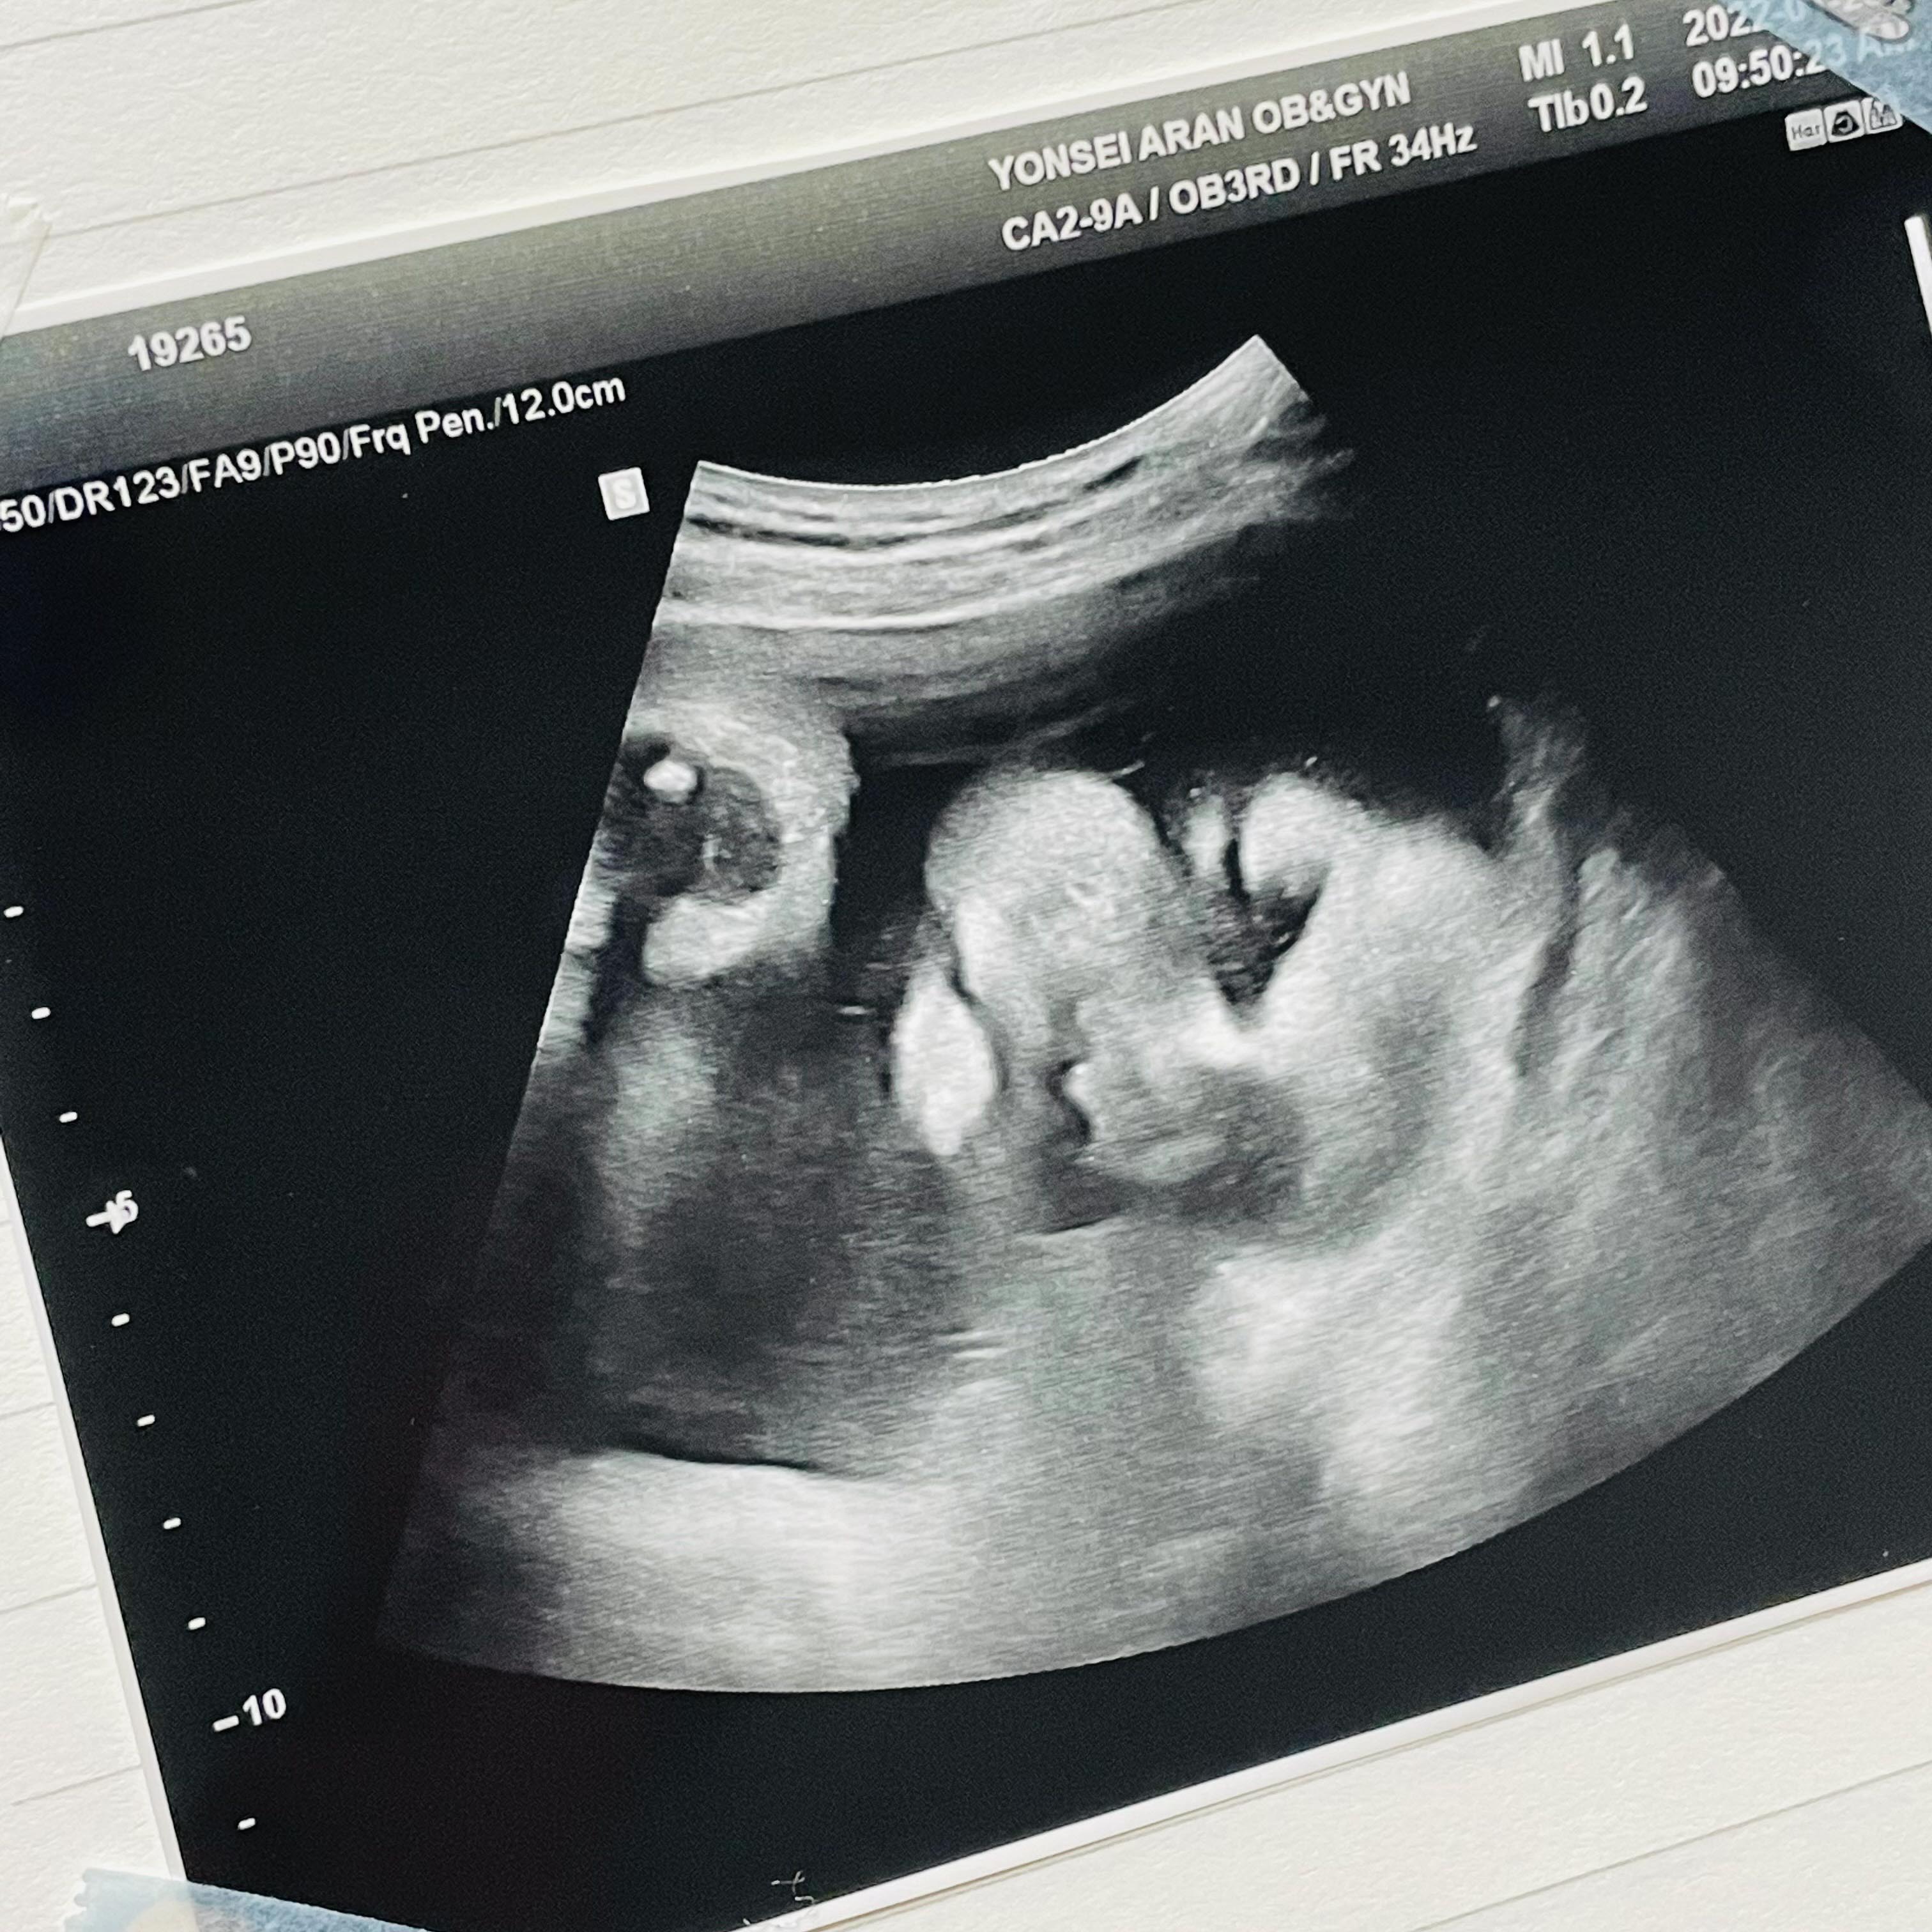

35주 1일

웬일로 얼굴을 보여줬다.

붕어와 찐빵의 콜라보 같은 느낌!

코가 남편 닮은 것 같기도..

이제 포도는 2.5kg으로 언제태어나도 정상 분만으로 볼 수 있다고 하셨다.